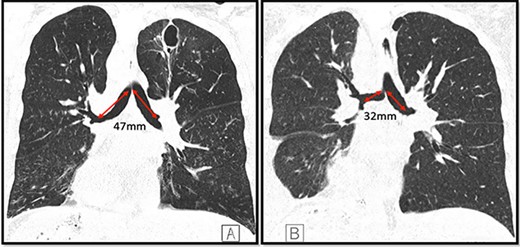

A 36-year-old female with past medical history of primary ciliary dyskinesia (PCD), chronic sinusitis and bronchiectasis with Pseudomonas Aeruginosa and Aspergillus colonization underwent bilateral lung transplantation. Based on the CT of the chest, both right and left main bronchi prior to lung transplantation were 47 mm in length, with a carinal bifurcation angle of ~55° (Fig. 1A). Prior to lung transplantation she had bi-lobed right and left lungs, with a right main bronchus which was as long as the left, which is a feature of situs ambiguous, i.e. left isomerism (bilateral left-sidedness). She had normal atrio-ventricular and ventriculo-arterial morphology though her cardiac apex was mildly shifted to the right (dextrocardia). Post transplantation, she was admitted as an outpatient for evaluation of declining lung function as detected on pulmonary function tests. She underwent repeat CT and bronchoscopy with transbronchial biopsies to evaluate for graft rejection. Interestingly, after transplantation her repeat CT (Fig. 1B) and surveillance bronchoscopy (Fig. 2A–C) revealed both right and left main bronchi that were 32 mm in length, with a normal tri-lobed right lung and a bi-lobed left lung. The right main bronchus was now at a right angle (90°) with the trachea. The composite bronchopulmonary situs was the result of isomeric recipient main bronchi (situs ambiguous) and normal donor lungs (situs solitus).

Coronal CT images depicting both main bronchi with the length of 47 mm prior to the lung transplantation (A); length of both main bronchi post transplantation is ~32 mm; the right main bronchus is now at an approximate right angle with the trachea (B); note the presence of dextrocardia in both images and a thin-walled postinfectious left upper lobe cavity in the native lung.

In our patient, the lengths of the right and left main bronchi prior to lung transplantation were 47 mm each, which was suggestive of left-sided isomerism. Notably, her post transplantation CT (Fig. 1B) and bronchoscopy (Fig. 2A–C) revealed both main bronchi to be of equal length (32 mm), which was longer than a normal right-sided bronchus (20 mm) yet shorter than a normal left-sided bronchus (50 mm). The right main bronchus was now at a right angle with the trachea and connected to a normal tri-lobed donor lung, while the left bronchus was anastomosed to a normal bi-lobed donor lung.

During lung transplantation the bronchial anastomosis is kept close to the bifurcation of the main bronchus to allow retrograde revascularization via bronchial arteries and to reduce risk of ischemic complications [3]. Thus, our patient with left-sided bronchial isomerism ended up with intermediate equal-length main-stem bronchi to facilitate surgical bronchial anastomosis with normal donor lungs (Fig. 1B). The histopathological samples obtained during the biopsy showed no evidence of rejection. Patient was discharged in stable condition to follow-up with her transplant pulmonologist.